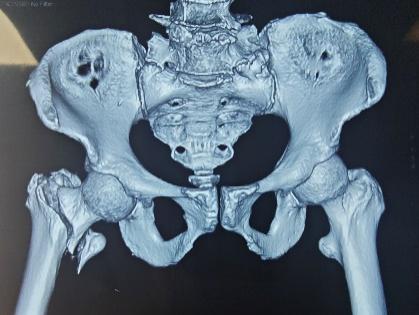

第一次内固定术后X线片及CT

此次入院前X线片及CT

怀着最后一线希望,谈大妈与家属慕名来到陕西省核工业二一五医院创伤骨科寻求诊治。吴超副主任医师接诊后,立即为谈大妈安排了详细且全面的检查,经影像检查发现,虽然粗隆间骨折已愈合,但此前植入的部分内固定物竟突破了股骨头、侵入髋臼,导致股骨头已坏死变形、髋臼骨质缺损。